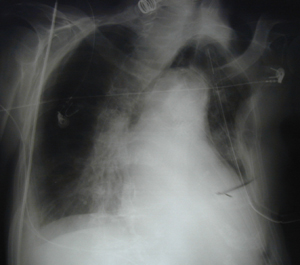

Εικόνα 1

Οπισθιοπροσθία ακτινογραφία θώρακος όπου υπάρχει πλήρης κατάληψη του αριστερού ημιθωρακίου από υγρό που προκαλεί μετατόπιση του μεσοθωρακίου προς την υγιή πλευρά. Ο ασθενής παρουσιάστηκε με έντονη δύσπνοια, και από το ιατρικό ιστορικό του ο ασθενής ανέφερε την λήψη αντιπηκτικών.